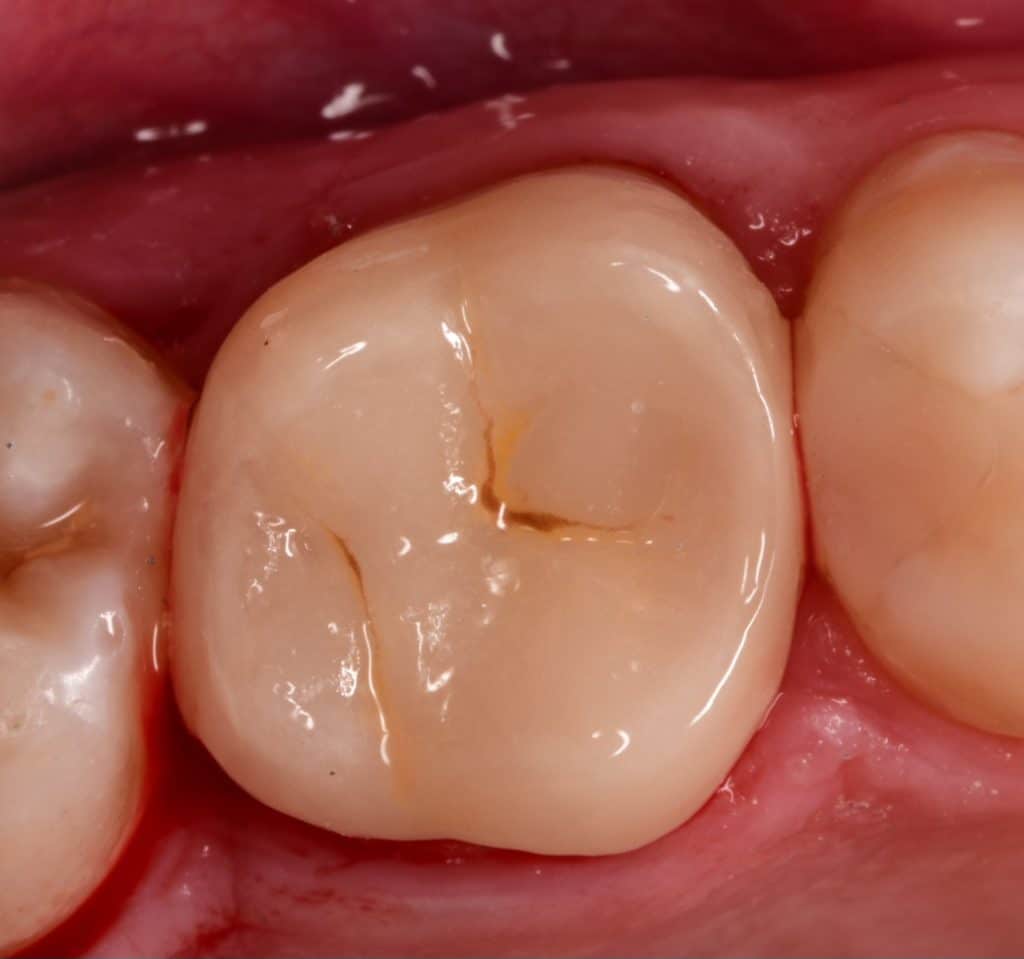

Immediate result

Final result